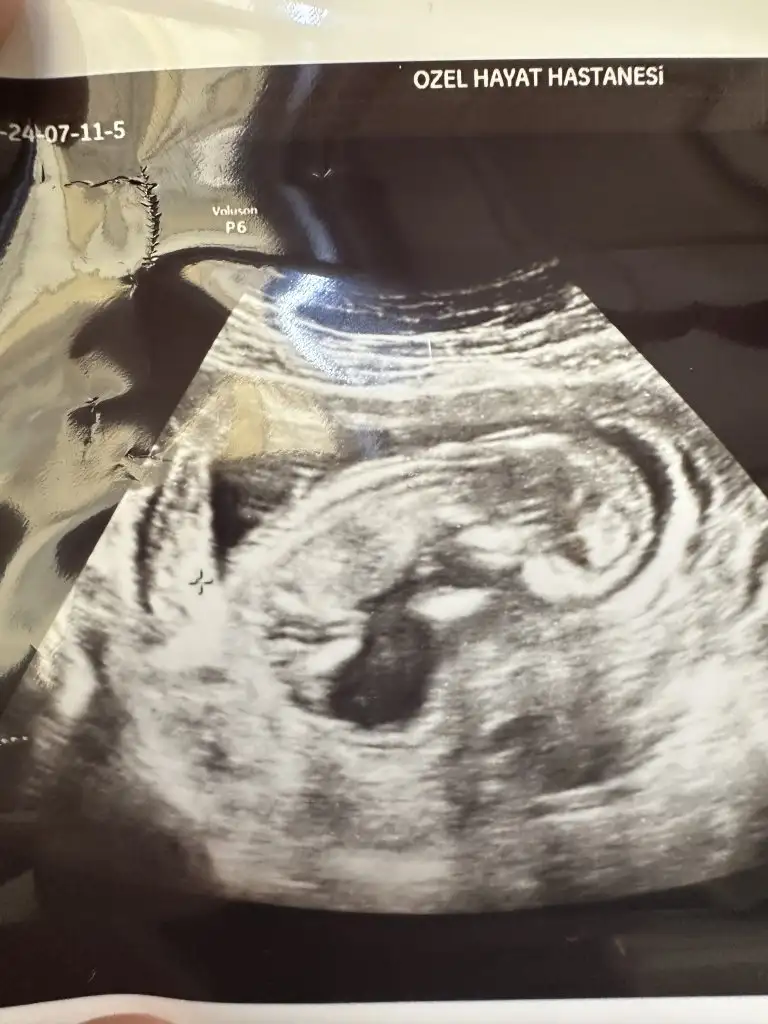

Merhaba bende yorum istiyorum 12 haftalık bebeğim